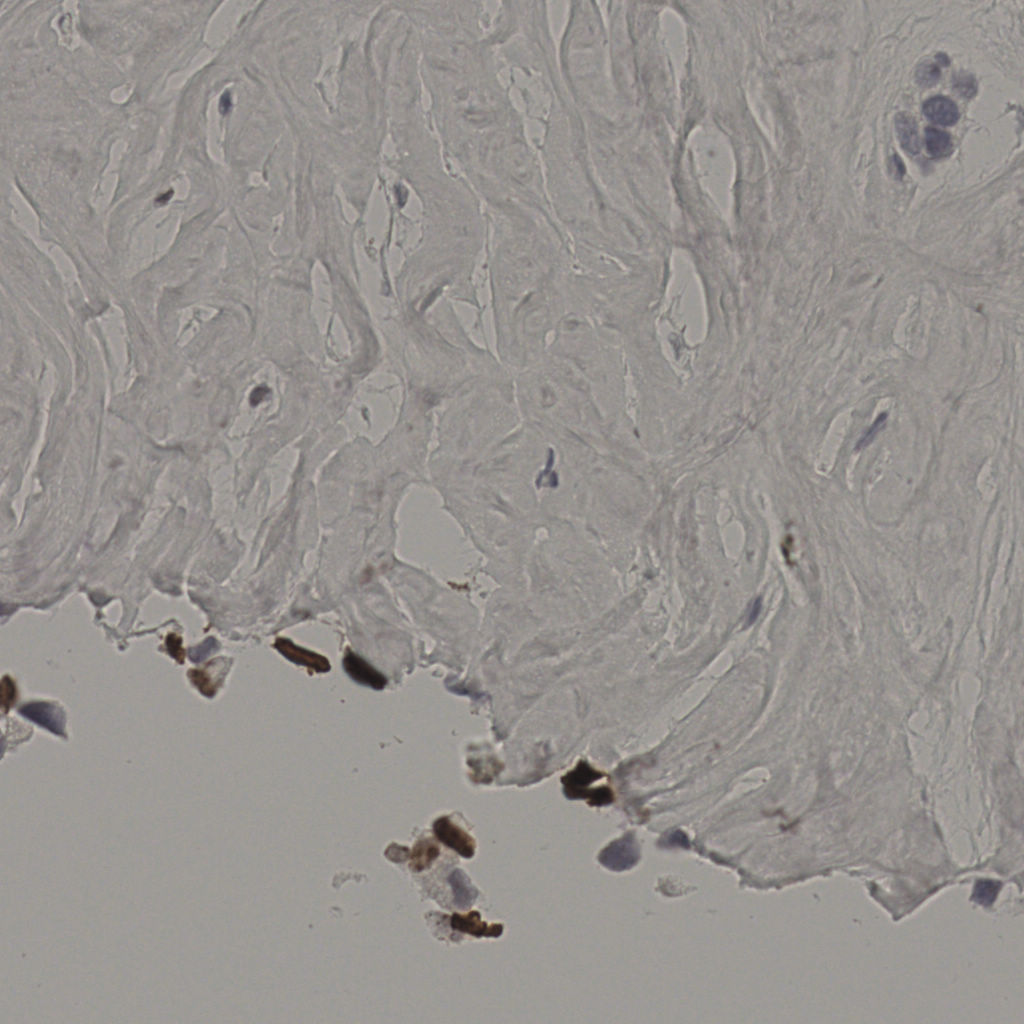

20240285Ki-67.ndpi

slice_21_41_x18816_y36736.png

slice_21_42_x18816_y37632.png

slice_21_44_x18816_y39424.png

slice_21_9_x18816_y8064.png